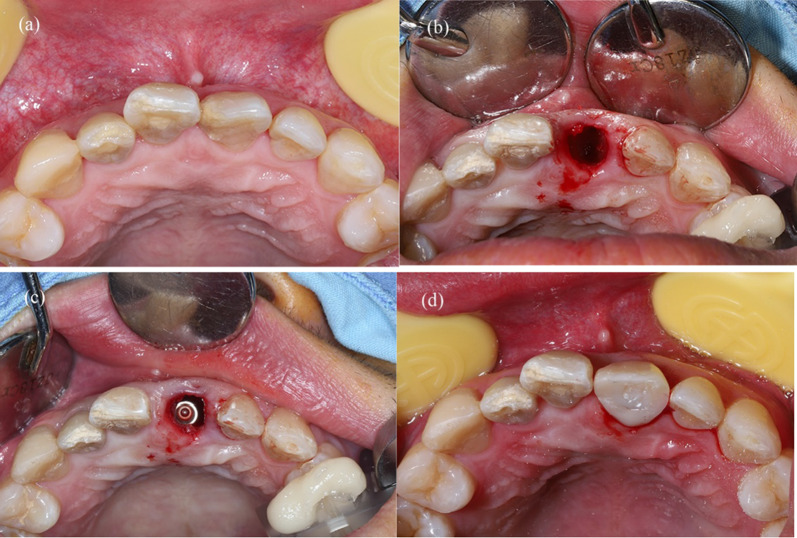

Fig. 2.

Surgical procedure for the static CAIS group. a Clinical observation of the hopeless tooth before surgery. b Extraction of 11. c Immediate implant placement with the fully guided static template. d Buccal gap was filled with bone substitute material and pre-fabricated temporary restoration was screwed